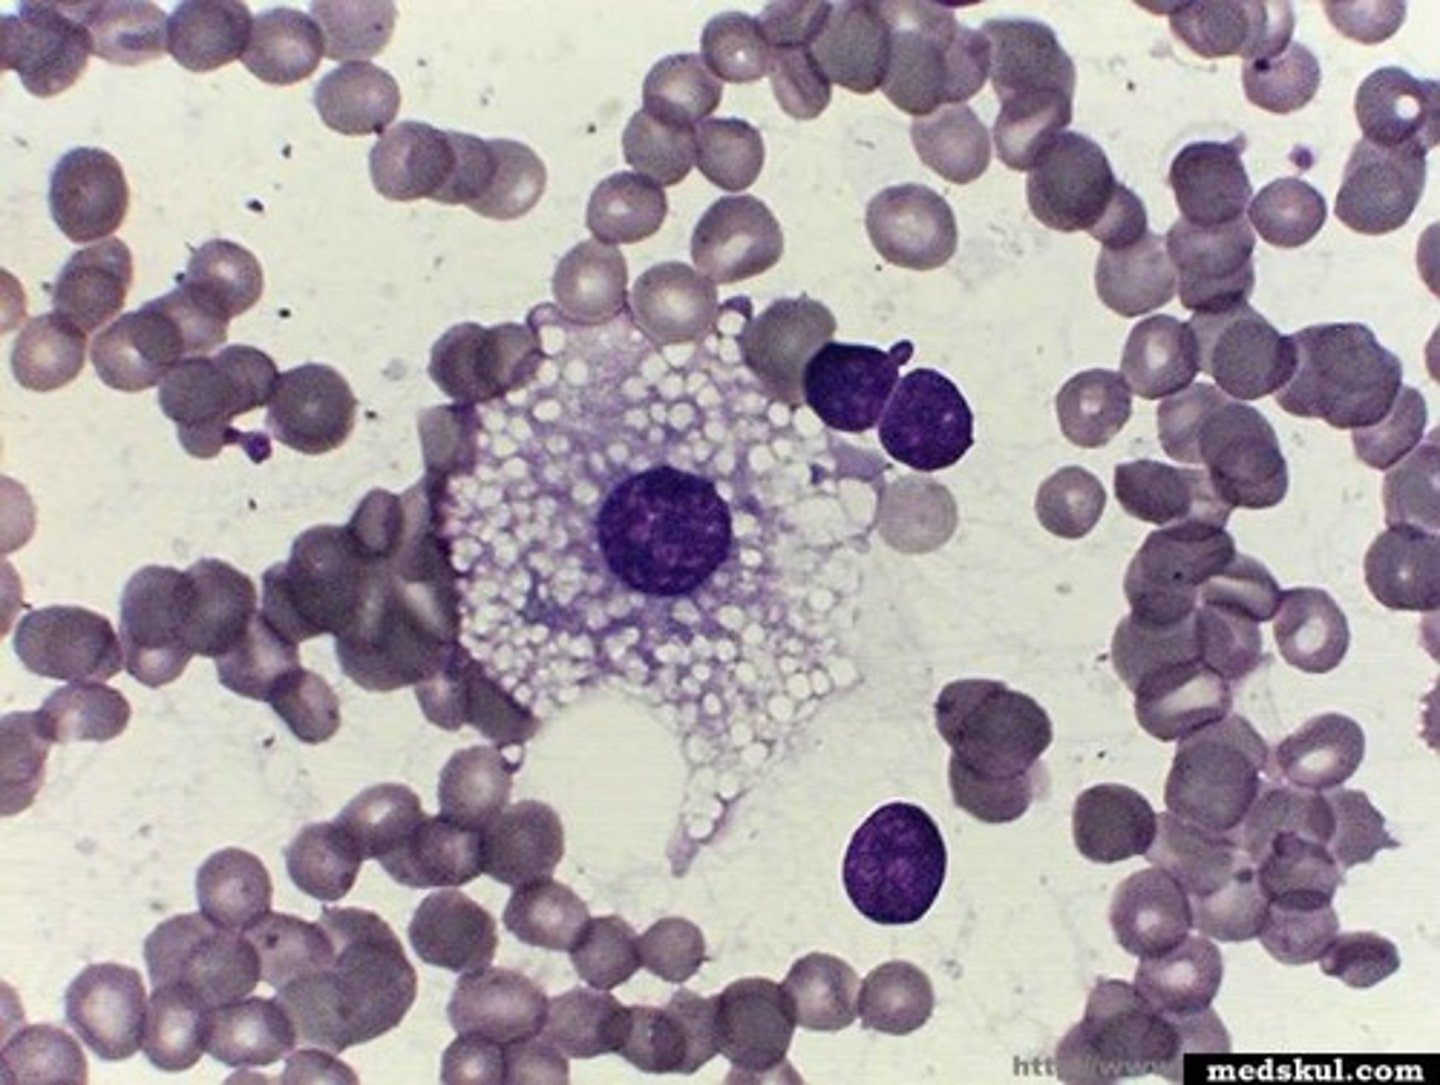

Blood

What is this?

Abnormal

Is this blood slide normal or abnormal?

Macrophage

what is this?